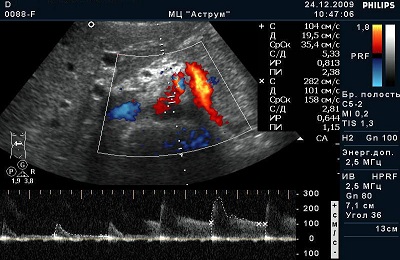

Триплекс – это краткое название такой диагностической процедуры, как триплексное сканирование сосудов.

В настоящее время именно данный вариант ультразвукового сканирования является наиболее информативным методом диагностики ангиологической патологии.

Максимальная информативность триплекса обусловлена тем, что такой вариант исследования включает в себя целых 3 ультразвуковых режима:

- собственно ультразвук;

- допплер;

- цветное допплеровское картирование.

Отличия триплексного и дуплексного сканирования. Первый режим дуплексного сканирования — это обычное ультразвуковое исследование, допплеровский режим позволяет получить график движения крови. Триплексное сканирование — это исследование в трех режимах: УЗИ, допплер и цветное картирование.